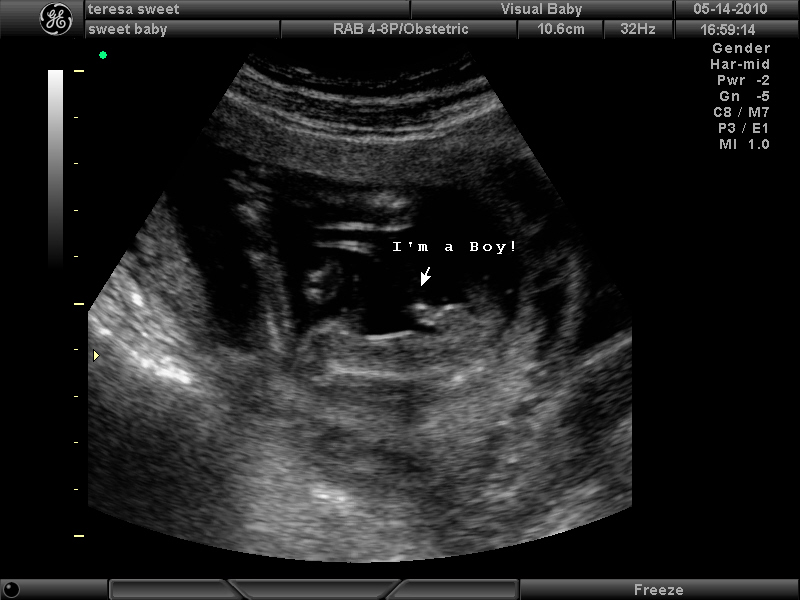

DRUUUUUUM Roll please……….

*** Meet Tyler Jack Sweet…due October 24, 2010 *** The boys are very excited to meet their baby brother!